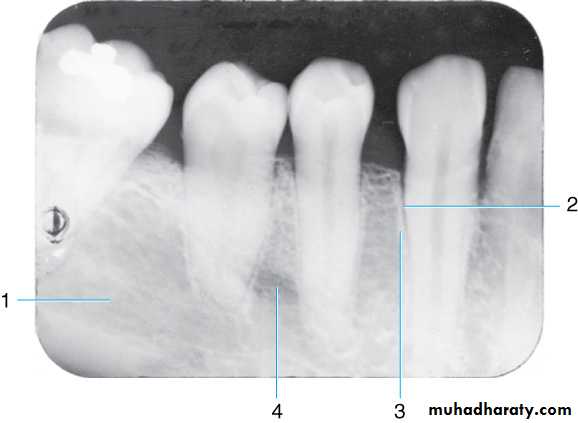

Radiograph of mandibular molar area. Shown are the (1) oblique ridge (buccal), (2) mylohyoid ridge (lingual) (3) mandibular canal, and (4) submandibular fossa

Radiograph of mandibular molar area. Shown are the

(1) Ext oblique ridge,(2) mylohyoid or internal oblique ridge,(3) mandibular canal and

(4) submandibular fossa